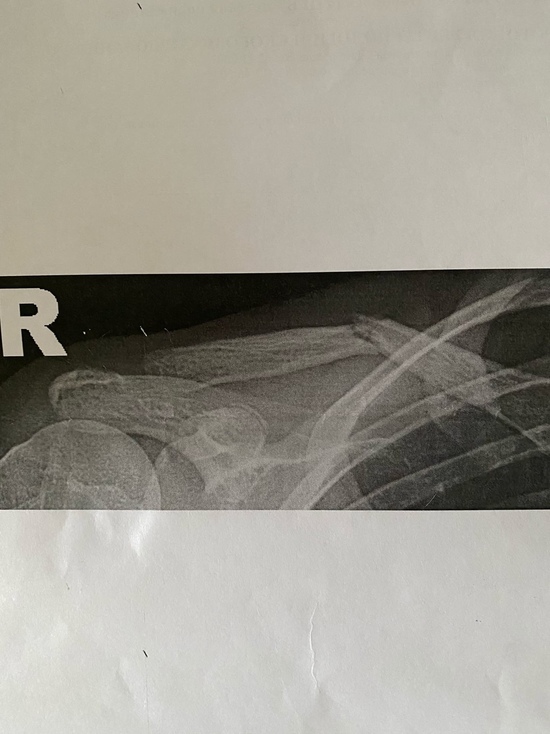

02.07.2021, 03:02 815 Перелом со смещением: врач из Ноябрьска назначил лечение мазью девочке со сломанной ключицей